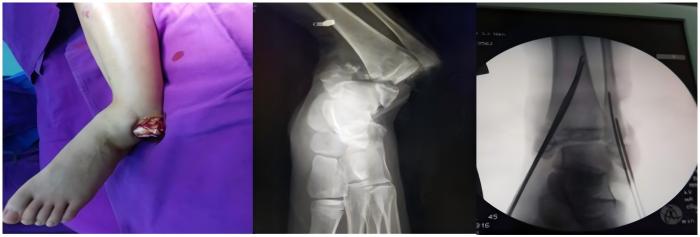

四、小儿骨科医学组:为了造福广大患儿,三院骨科特别引进小儿骨科专家张春辉主任,(我市仅有的两位专业小儿骨科专家之一)。先后开展儿童先天性髋关节发育不良、儿童骨折、骨骺损伤、发育畸形等各种疾病的手法修复和手术修复,治疗效果满意。

小儿开放性踝骨折脱位并骨骺损伤的治疗

骨折的微创固定手术